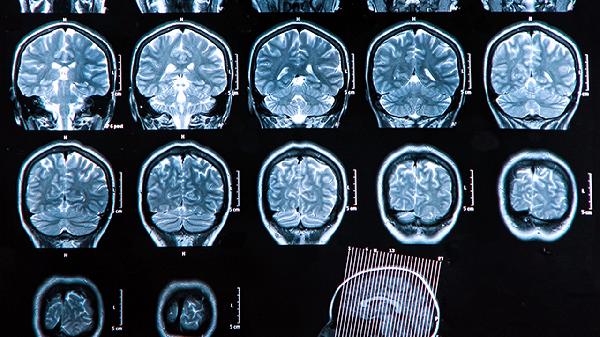

脑血栓片主要用于治疗脑血栓形成及脑梗死。这类患者通常存在头痛、言语不清、肢体麻木或偏瘫等症状,经CT或MRI检查可见脑组织缺血性病灶。该药通过抑制血小板聚集、改善脑微循环发挥治疗作用。常见药物如脑血栓片常与阿司匹林肠溶片、尼莫地平片等联合使用。